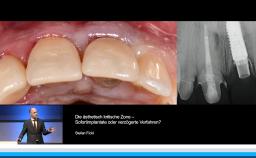

Er definiert kurze Implantate als kleiner gleich 8 mm und vergleicht diese mit längeren Implantaten größer gleich 12 mm. Dabei geht er auch knapp auf prothetische Aspekte der Versorgung kurzer Implantate, sowie die Frage des Belastungszeitpunktes auf der Basis der ISQ Messung, ein. An klinischen Fällen zeigt er den Sinn des Einsatzes von Soft Tissue Level Implantaten in dieser Indikation auf.

- die Bedeutung von Soft Tissue Level Implantaten im seitlichen Unterkiefer kennen